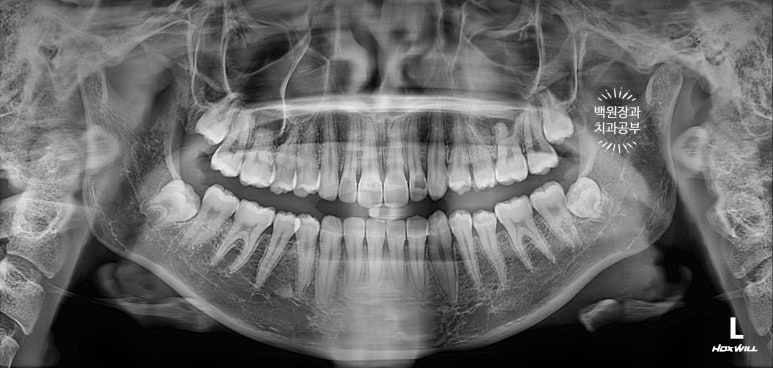

그 날 찍었던 치과용 파노라마 엑스레이 사진입니다.

사랑니가 매복되어 있다는 것 말곤.. 크게 문제가 없어 보였어요!!